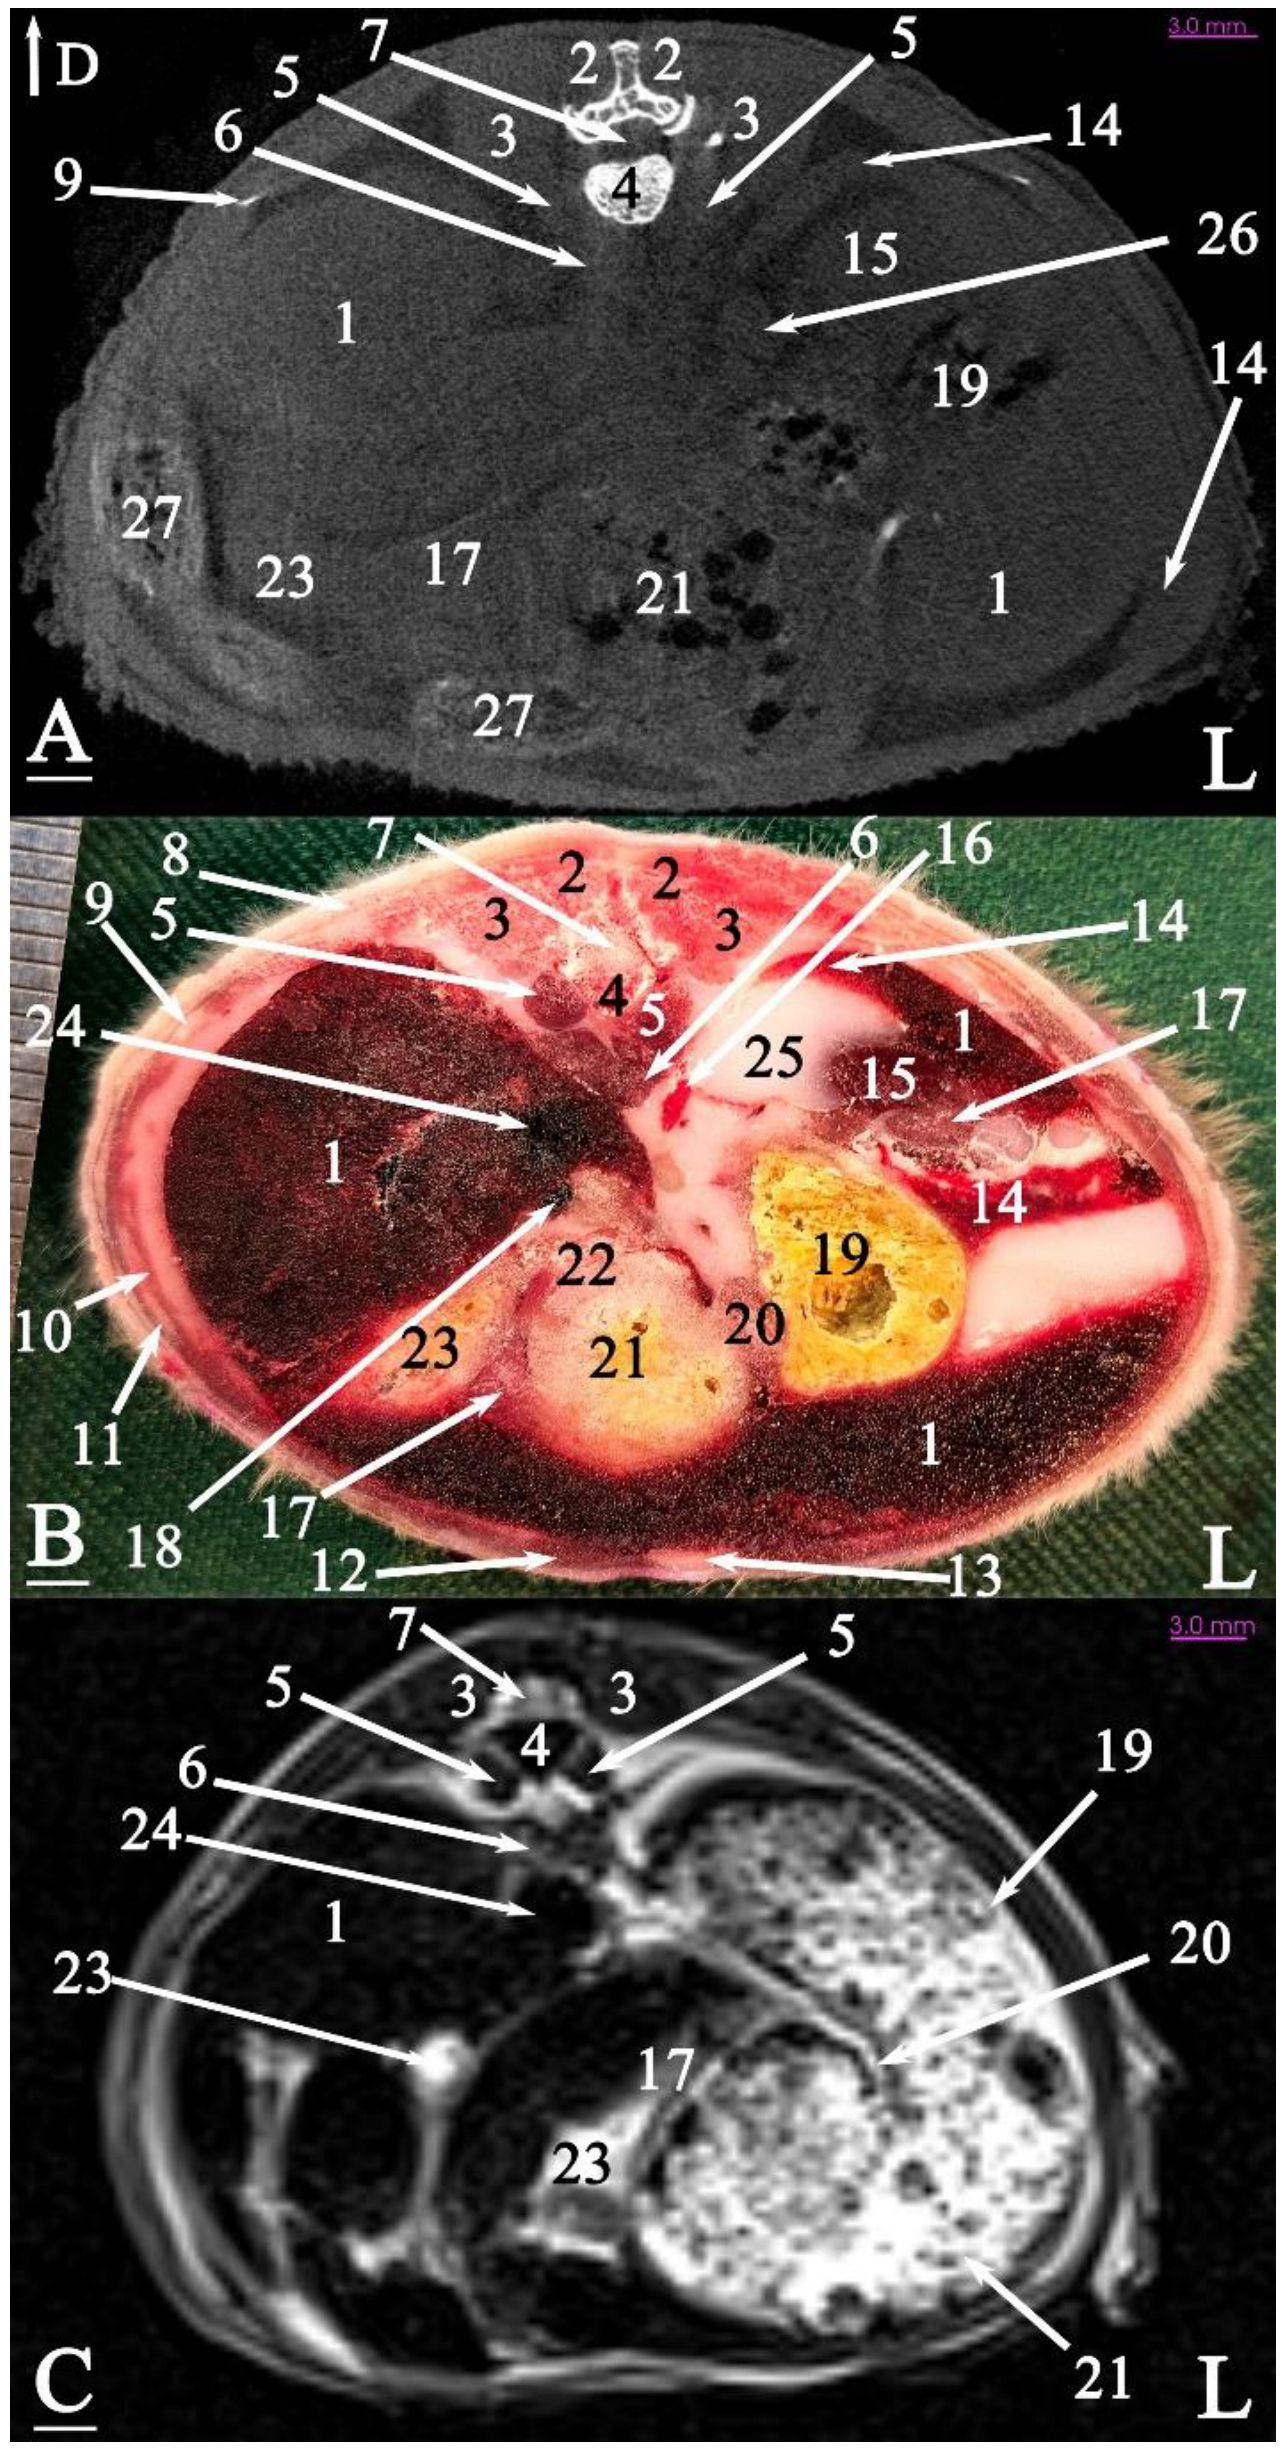

3.2. Anatomical Sectioning

3.2.1. Transverse Cadaver Slices

3.3. Micro-CT Slices

3.4. MRI Slices